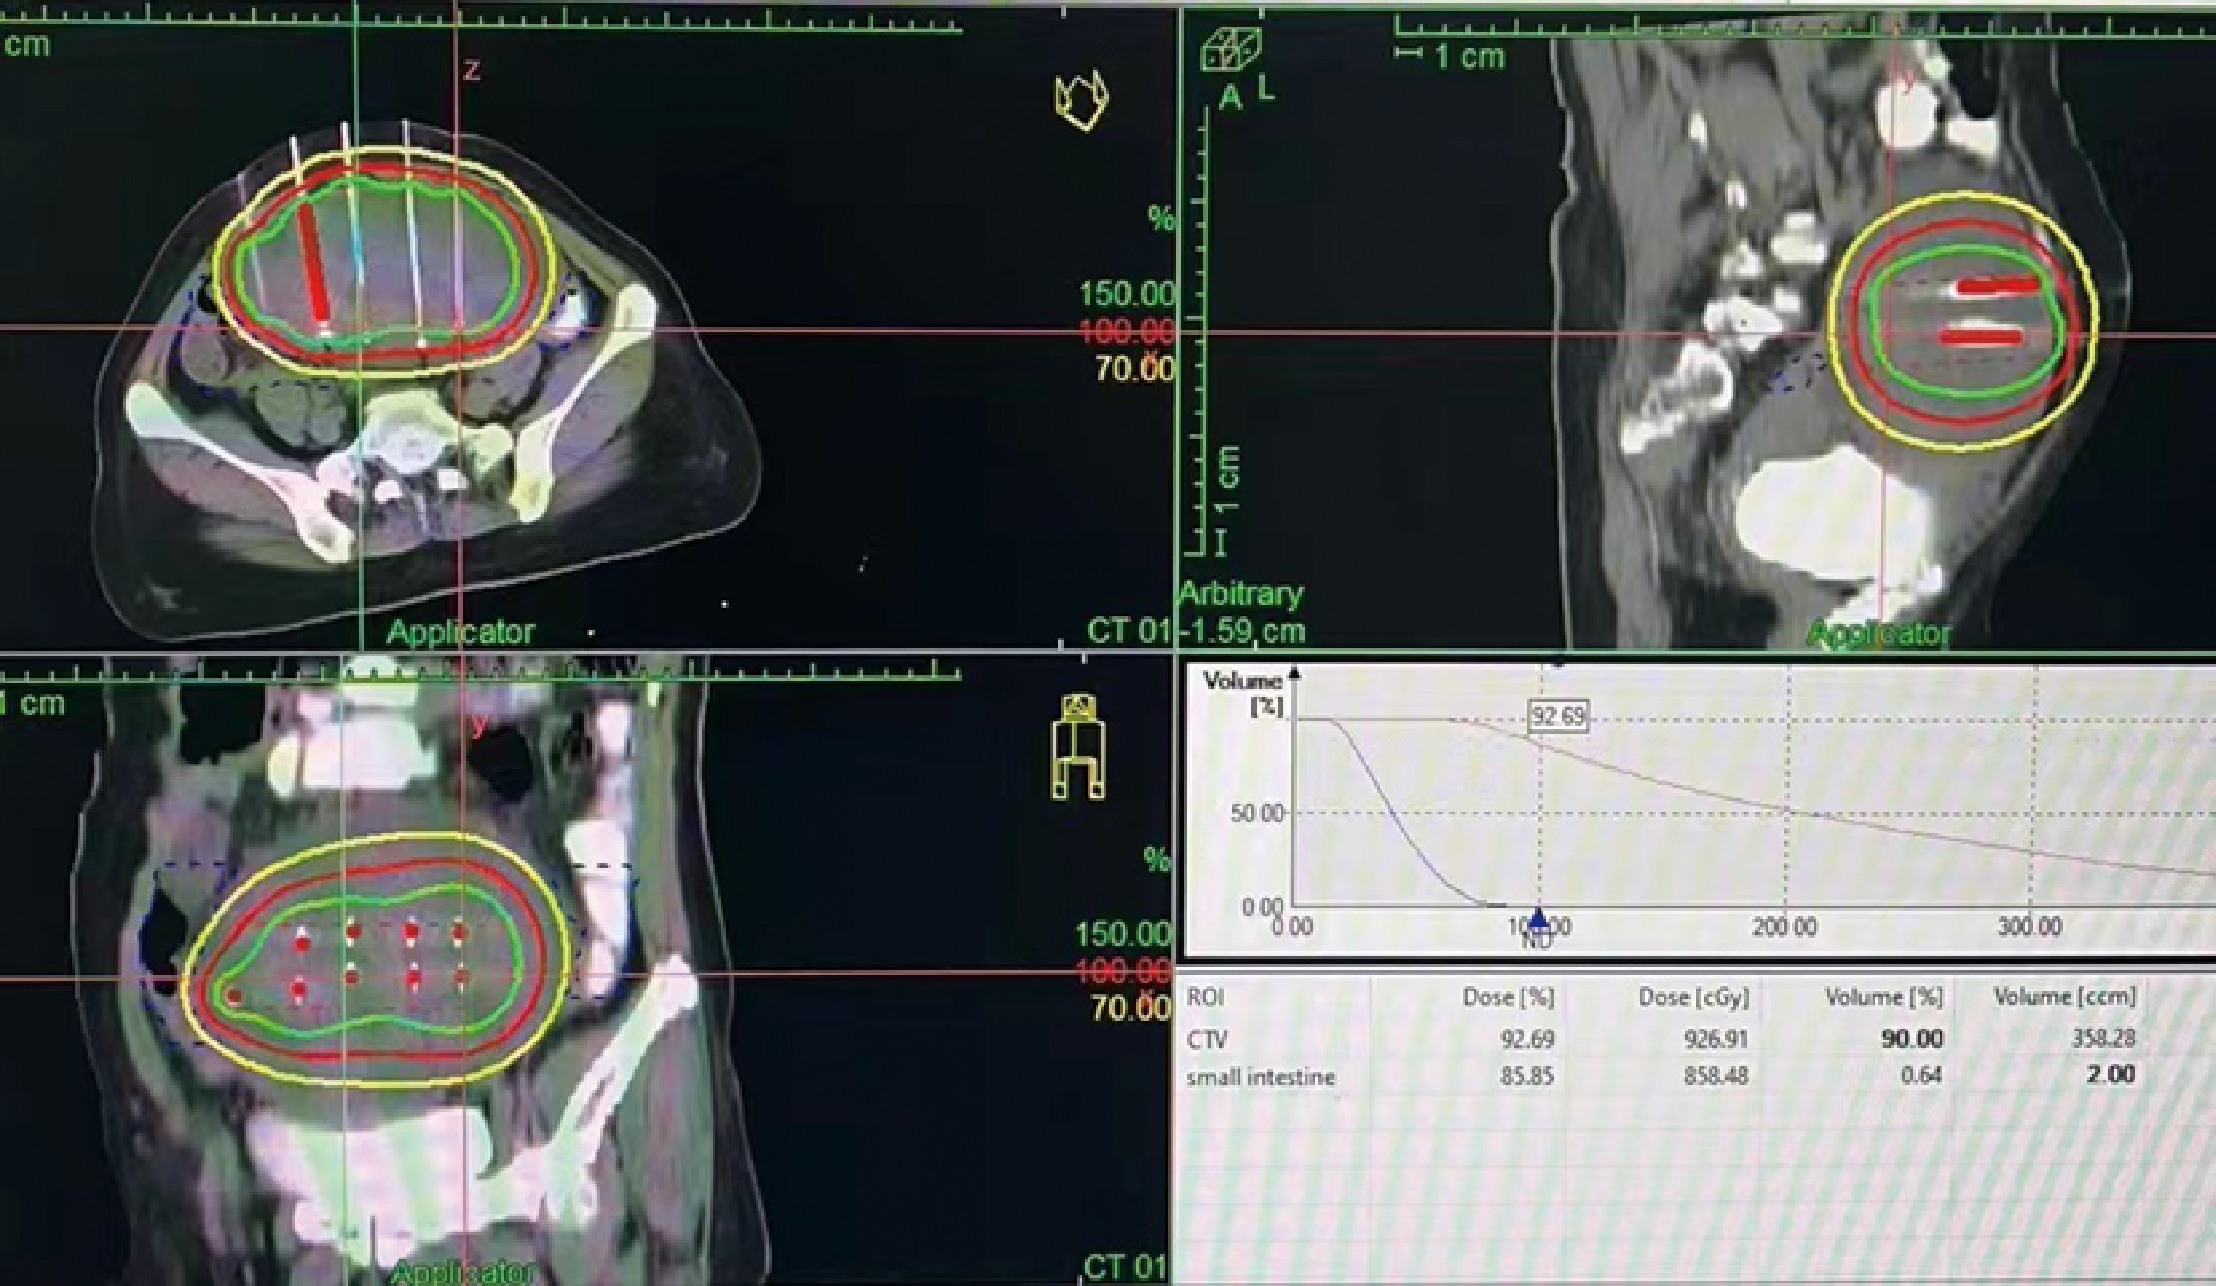

In February 2022, the patient experienced abdominal distension again along with a large amount of ascites. In July 2022, the patient was readmitted to our hospital with a worsening condition. Abdominal CT suggested a cystic solid mass in the pelvis (size 12.5×10.6 cm) and CA125 was 1175.16 U/ml and HE4 was 133.80 pmol/L. Tumor recurrence was considered. From July 2022 to November 2022, the patient received 7 cycles of systemic therapy with a targeted agent in combination with a chemotherapeutic agent. On the clinician’s recommendation, the patient received 1 cycle of bevacizumab in combination with irinotecan (bevacizumab 7.5 mg/kg + irinotecan 60 mg/kg, ivgtt, q21d), 1 cycle of bevacizumab in combination with albumin-paclitaxel (bevacizumab 7.5 mg/kg + albumin-paclitaxel q21d), and 5 cycles of bevacizumab in combination with eribulin (bevacizumab 7.5mg/kg + eribulin 2mg d1, d8, q21d). During the treatment, the pelvic mass of the patient was still increasing, and the general condition was getting worse. The patient refused to undergo palliative surgery to relieve symptoms and to be enrolled in clinical studies. Considering that the patient has experienced multiple relapses with the same pelvic lesion and the lesion is isolated, local radiotherapy combined with immunotherapy was chosen. Due to financial reasons, the patient refused immune-related genetic tests, including microsatellite instability (MSI) status, programmed cell death-ligand 1 (PD-L1), and tumor mutation burden (TMB). However, considering the MSI-H/dMMR incidence of up to 30% (11), our patient strongly expressed her willingness to do immunotherapy and chose the relatively affordable and cheap the PD-1 inhibitor tirilizumab produced in China. We informed our patient of the treatment purpose and risks, and signed an informed consent form. The patient then received triple therapy from November 30, 2022. The radiation oncologist implemented interstitial implantation radiotherapy at a prescribed dose of 10 Gy, combined with a subcutaneous injection of GM-CSF (200 µg) for one week. The tumor got an actual dose of 926.91 cGy. On December 2, 2022, the patient began immunotherapy with the PD-1 inhibitor tirilizumab (300 mg, ivgtt). Figure 2 shows the three-dimensional conformal dose assessment for interstitial implantation radiation therapy. After radiotherapy, the patient developed mild localized erythema. The patient now has no skin ulcers, no bilateral lower extremity edema or other complications, and only mild localized skin pigmentation. The patient’s efficacy evaluation showed a PR. After that, single-agent maintenance therapy with the PD-1 inhibitor tirilizumab was administered every three weeks. During immune maintenance therapy, the patient was temporarily free of treatment-related adverse events (TRAEs), like hemopoietic, thyroid, lung, and heart dysfunction. As of the follow-up in June 2023, abdominal CT suggested a smaller pelvic mass than before (Figure 3) and CA125 was persistently decreasing (most recent CA125 was 18.30 U/ml) (Figure 4). The patient’s lesion achieved a PR and continues to benefit for more than six months.

Figure 2

Interstitial implantation radiotherapy: Three-dimensional conformal dose assessment.